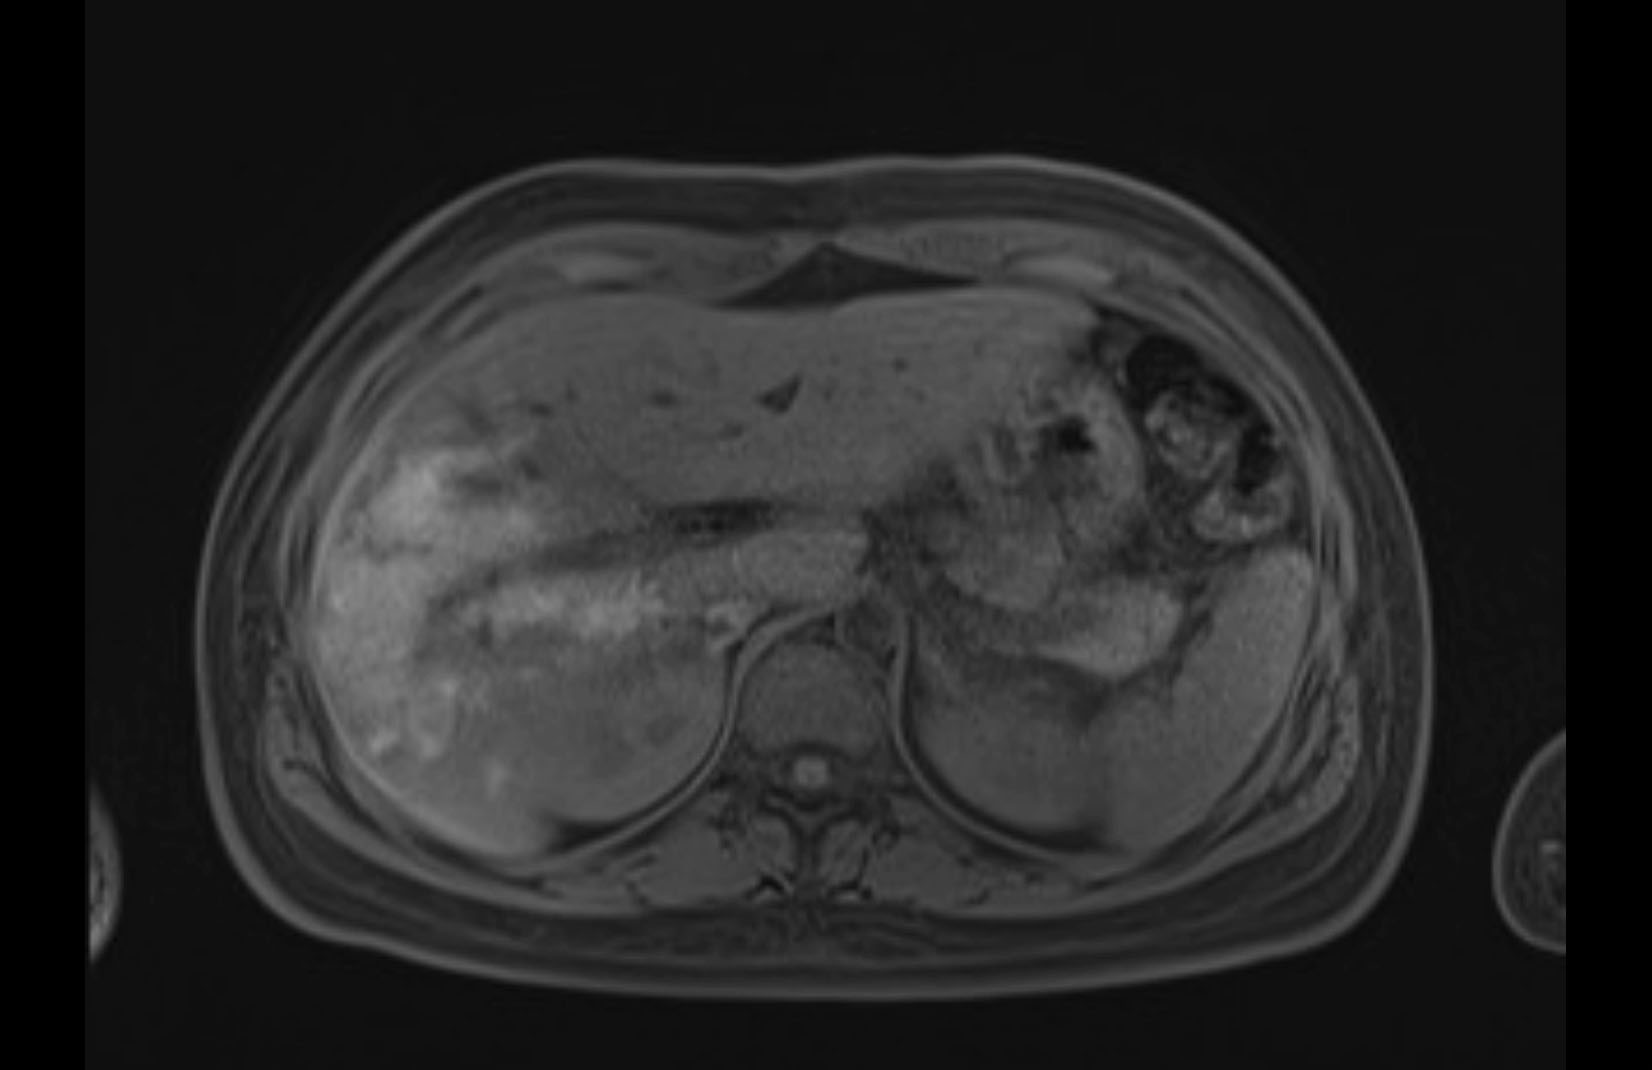

MRI T1

MRI T2